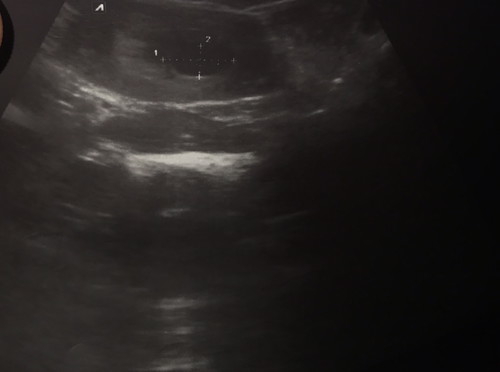

คือแบบเรามีไรจะถามค่ะคือแบบตอนนี้เราท้องได้2เดือนแล้วแต่ยังไม่เห็นตัวเด็กค่ะมีแต่ถุงจะเป็นไรไหมค่ะหรือว่ายังไง

น้องอาจจะยังเล็กเลยไม่เจอค่ะแม่ รออีกนิดถ้ายังไม่เจอก็ท้องลมค่ะ